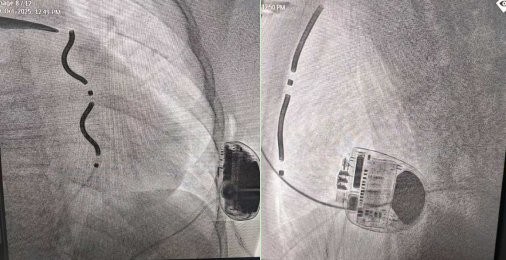

术中植入EV-ICD后的图像

10月29日上午,心胸外科邓喜成主任医师、心血管内科王野峰副主任医师、左超主治医师、麻醉科专家肖婷主任医师等专家协同合作,为患者实施EV-ICD植入手术。术中通过胸骨下方微小切口,团队将专用血管外除颤导线精准植入胸骨后间隙,并与埋置于左侧腋下的除颤器主机相连接。该导线系统完全避开心脏和血管,借助胸骨后贴近心脏的解剖位置,实现了对心律失常的监测与治疗功能。术中按标准程序进行了严格的系统测试,通过程序电刺激诱发出持续性室性心动过速,EV-ICD系统即刻准确识别并成功实施转复治疗。测试数据显示,该系统心律失常识别灵敏度达100%,除颤效能与经典经静脉ICD相当,各项参数完全符合临床预期。